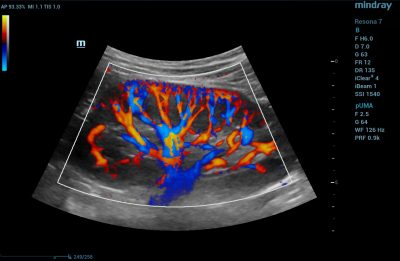

- Kidneys – CDI is used in renal ultrasonography to assess kidney issues such as renal hypertension, renal vein thrombosis, tumors, and hypovolemia – a condition that occurs from low blood volume.

Color Doppler Ultra Micro Angiography of Renal Cortex Perfusion